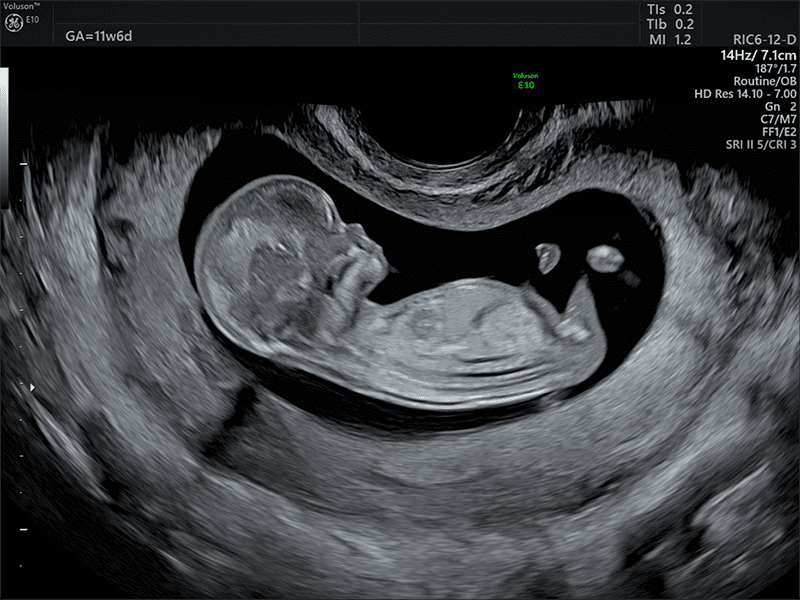

SonoBiometry: avanzato algoritmo intelligente di riconoscimento e misura delle principali references biometriche del feto.

SonoFHR: avanzato algoritmo intelligente di riconoscimento e misura automatica del ciclo cardiaco in M-Mode e Doppler Pulsato (PW).